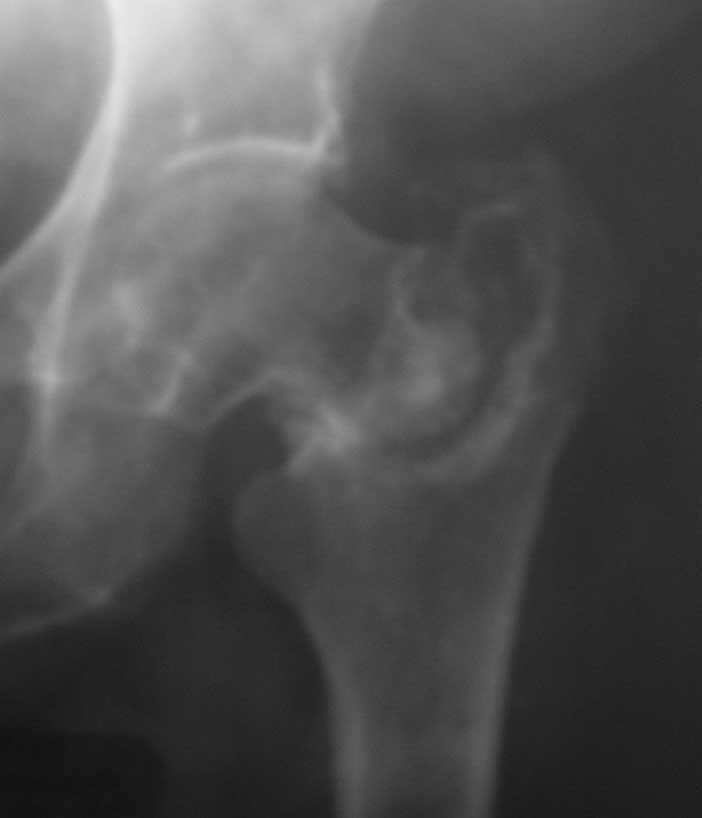

[Ortho] Ложный сустав базальной части шейки бедра

Больная 61 год. Травма 1 год назад – закрытый базальный перелом бедренной кости без смещения.

Перелом рентгенологически был диагностирован только через 6 недель (на первичных снимках

не визуализировался, КТ не проводилось, повторную травму отрицает). Проведен курс

консервативного лечения (ходьба на костылях без опоры на левую ногу до 4-х месяцев, ЛФК,

физиолечение и т.п.). В настоящее время передвигается при помощи костылей с незначительной

опорой на левую ногу. Больная страдает сахарным диабетом.

Возможные варианты лечения: 1) Тотальное эндопротезирование. 2) Ревизия ложного сустава, возможно костная пластика, МОС

углообразной пластиной 130, DHS, AFN.